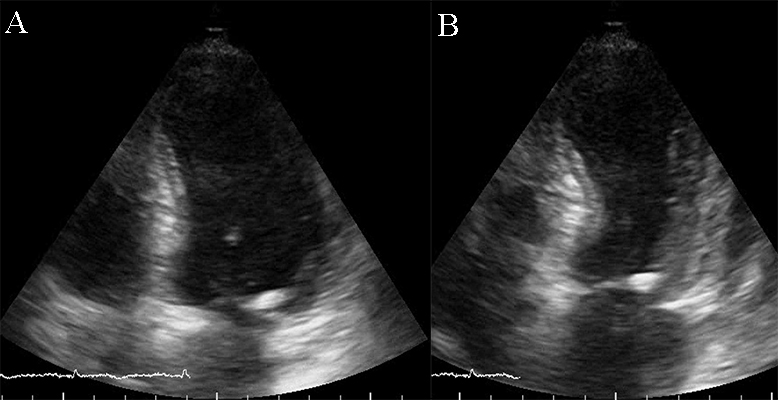

Fig. 2.Echocardiographic aspect of DCM in a patient with idiopathic dilated cardiomyopathy. (A) Parasternal short axis at the level of the mitral valve, diastolic frame showing a dilated left ventricle. (B) Parasternal short axis at the level of the mitral valve, systolic frame showing the small difference between the end-diastolic and end-systolic diameter of the left ventricle due to reduced contractility.

The initial imaging evaluation comprises of two main 2D echocardiography parameters: left ventricle ejection fraction (LVEF) less than 40% or fractional shortening less than 25% [6]. However, the comprehensive diagnosis of DCM should consider aspects of the clinical presentation, patient examination and other test results. Dilatation of the LV, especially end-diastolic and end-systolic transverse diameter enlargement (spherical remodeling), associated with reduced wall thickness, is easily recognized with 2D echocardiography in parasternal long-axis view (See Fig. 1 and Appendix Video 1).

Fig. 1.Echocardiographic aspect of DCM. Parasternal long-axis view showing a dilated left atrium and left ventricle in diastole. An online video of this patient with idiopathic dilated cardiomyopathy is available (Appendix Video 1).